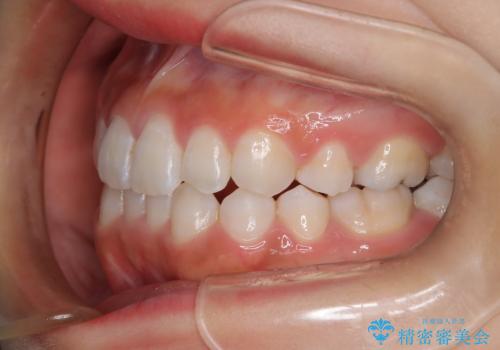

- 子供のころに矯正治療をされていたが、後戻りをしてしまったという20代女性の患者様です。上顎左右の2番が、咬合時に下顎の歯よりも内側に入っているクロスバイトという状態でした。奥歯の咬合関係は変えずに、マウスピース矯正にて前歯の並びを綺麗なアーチに仕上げました。再度後戻りしてしまうリスクを軽減させるために、リテーナー(保定装置)をお渡ししています。